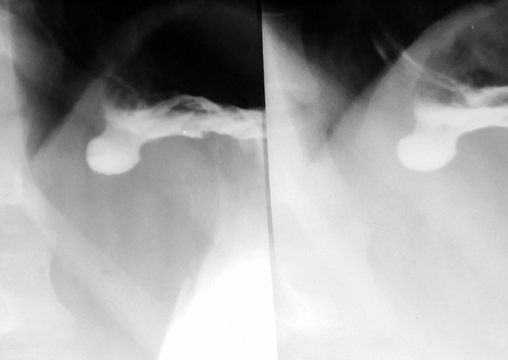

Ulcer gastric

Ulcer piloric